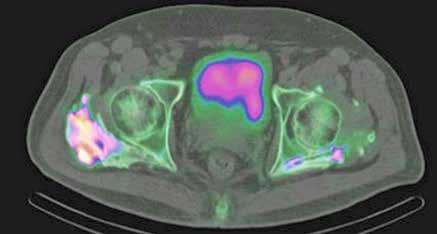

Figura 4.

TC realizado tras las dos embolizaciones arteriales. Vemos cómo la lesión ha disminuido considerablemente de tamaño y ahora está más alejada de las VSH y de la cava. Esto permite la ligadura de las VSH en su confluencia con la cava. Inicialmente no habría sido posible por su cercanía y tamaño.

Tres meses después se realiza un nuevo TC de control, que muestra la lesión en el mismo lugar, actualmente de 7,4x5,9 cm de diámetros (previo de 9,8x7,5 cm). En la actualidad se ha alejado de las VSH, pero contacta y desplaza la vena porta derecha y la arteria hepática. Además se visualiza una leve dilatación de la vía biliar intrahepática izquierda, de nueva aparición. Se presenta en comité una vez más y se decide colocar un drenaje biliar interno-externo, dado la dilatación de vía biliar que presenta el paciente. Además se realiza una embolización portal derecha, para así aumentar el remanente del hígado izquierdo que era del 29%. Se realiza una nueva volumetría hepática tras la embolización portal y se comprueba que el futuro remanente hepático había aumentado al 42%.

Resumiendo: Teníamos una masa hepática inicialmente irresecable que se ha tratado con dos embolizaciones arteriales, consiguiendo una disminución del tamaño y una mayor separación de las venas suprahepáticas. Sin embargo, se ha acercado a la bifurcación portal y comprime la vía biliar (dilata la vía intrahepática izquierda asociando una elevación de bilirrubina). Se ha colocado un drenaje biliar interno-externo. Se ha embolizado la porta derecha, consiguiendo pasar de un volumen de remante hepático del 29% al 42%, siendo ahora posible su resección. El acceso a las VSH sigue siendo complejo y arriesgado, pero menos que al inicio (Figura 4).